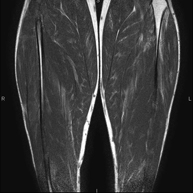

- Thigh MRI

Ideal examination for studying injuries to the hamstrings and quadriceps, which are frequently injured in athletes. It also allows for a good assessment of tendons and peripheral nerves. It lasts approximately 20 minutes. It is a radiation-free procedure.